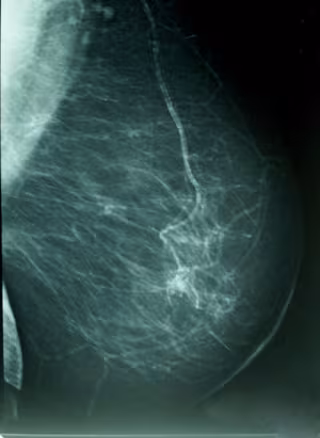

El estudio, publicado en la revista 'Breast Cancer Research and Treatment', explora la influencia de determinadas características con dicha densidad - la proporción de tejido radiológicamente blanco en la mamografía-, que es reconocido como un marcador de riesgo de cáncer de mama.

La investigación, realizada sobre una muestra 3.574 mujeres con edades comprendidas entre los 45 y los 68 años, analiza la influencia de ciertas características del nacimiento y la infancia de las mujeres con su densidad mamógrafica, un importante marcador de riesgo para cáncer de mama.

Además, otros trabajos demostraron que las mujeres que experimentan una reducción de la densidad mamaria en seis años presentan menos riesgo a desarrollar este cáncer, en comparación con aquellas cuya densidad se mantiene estable.